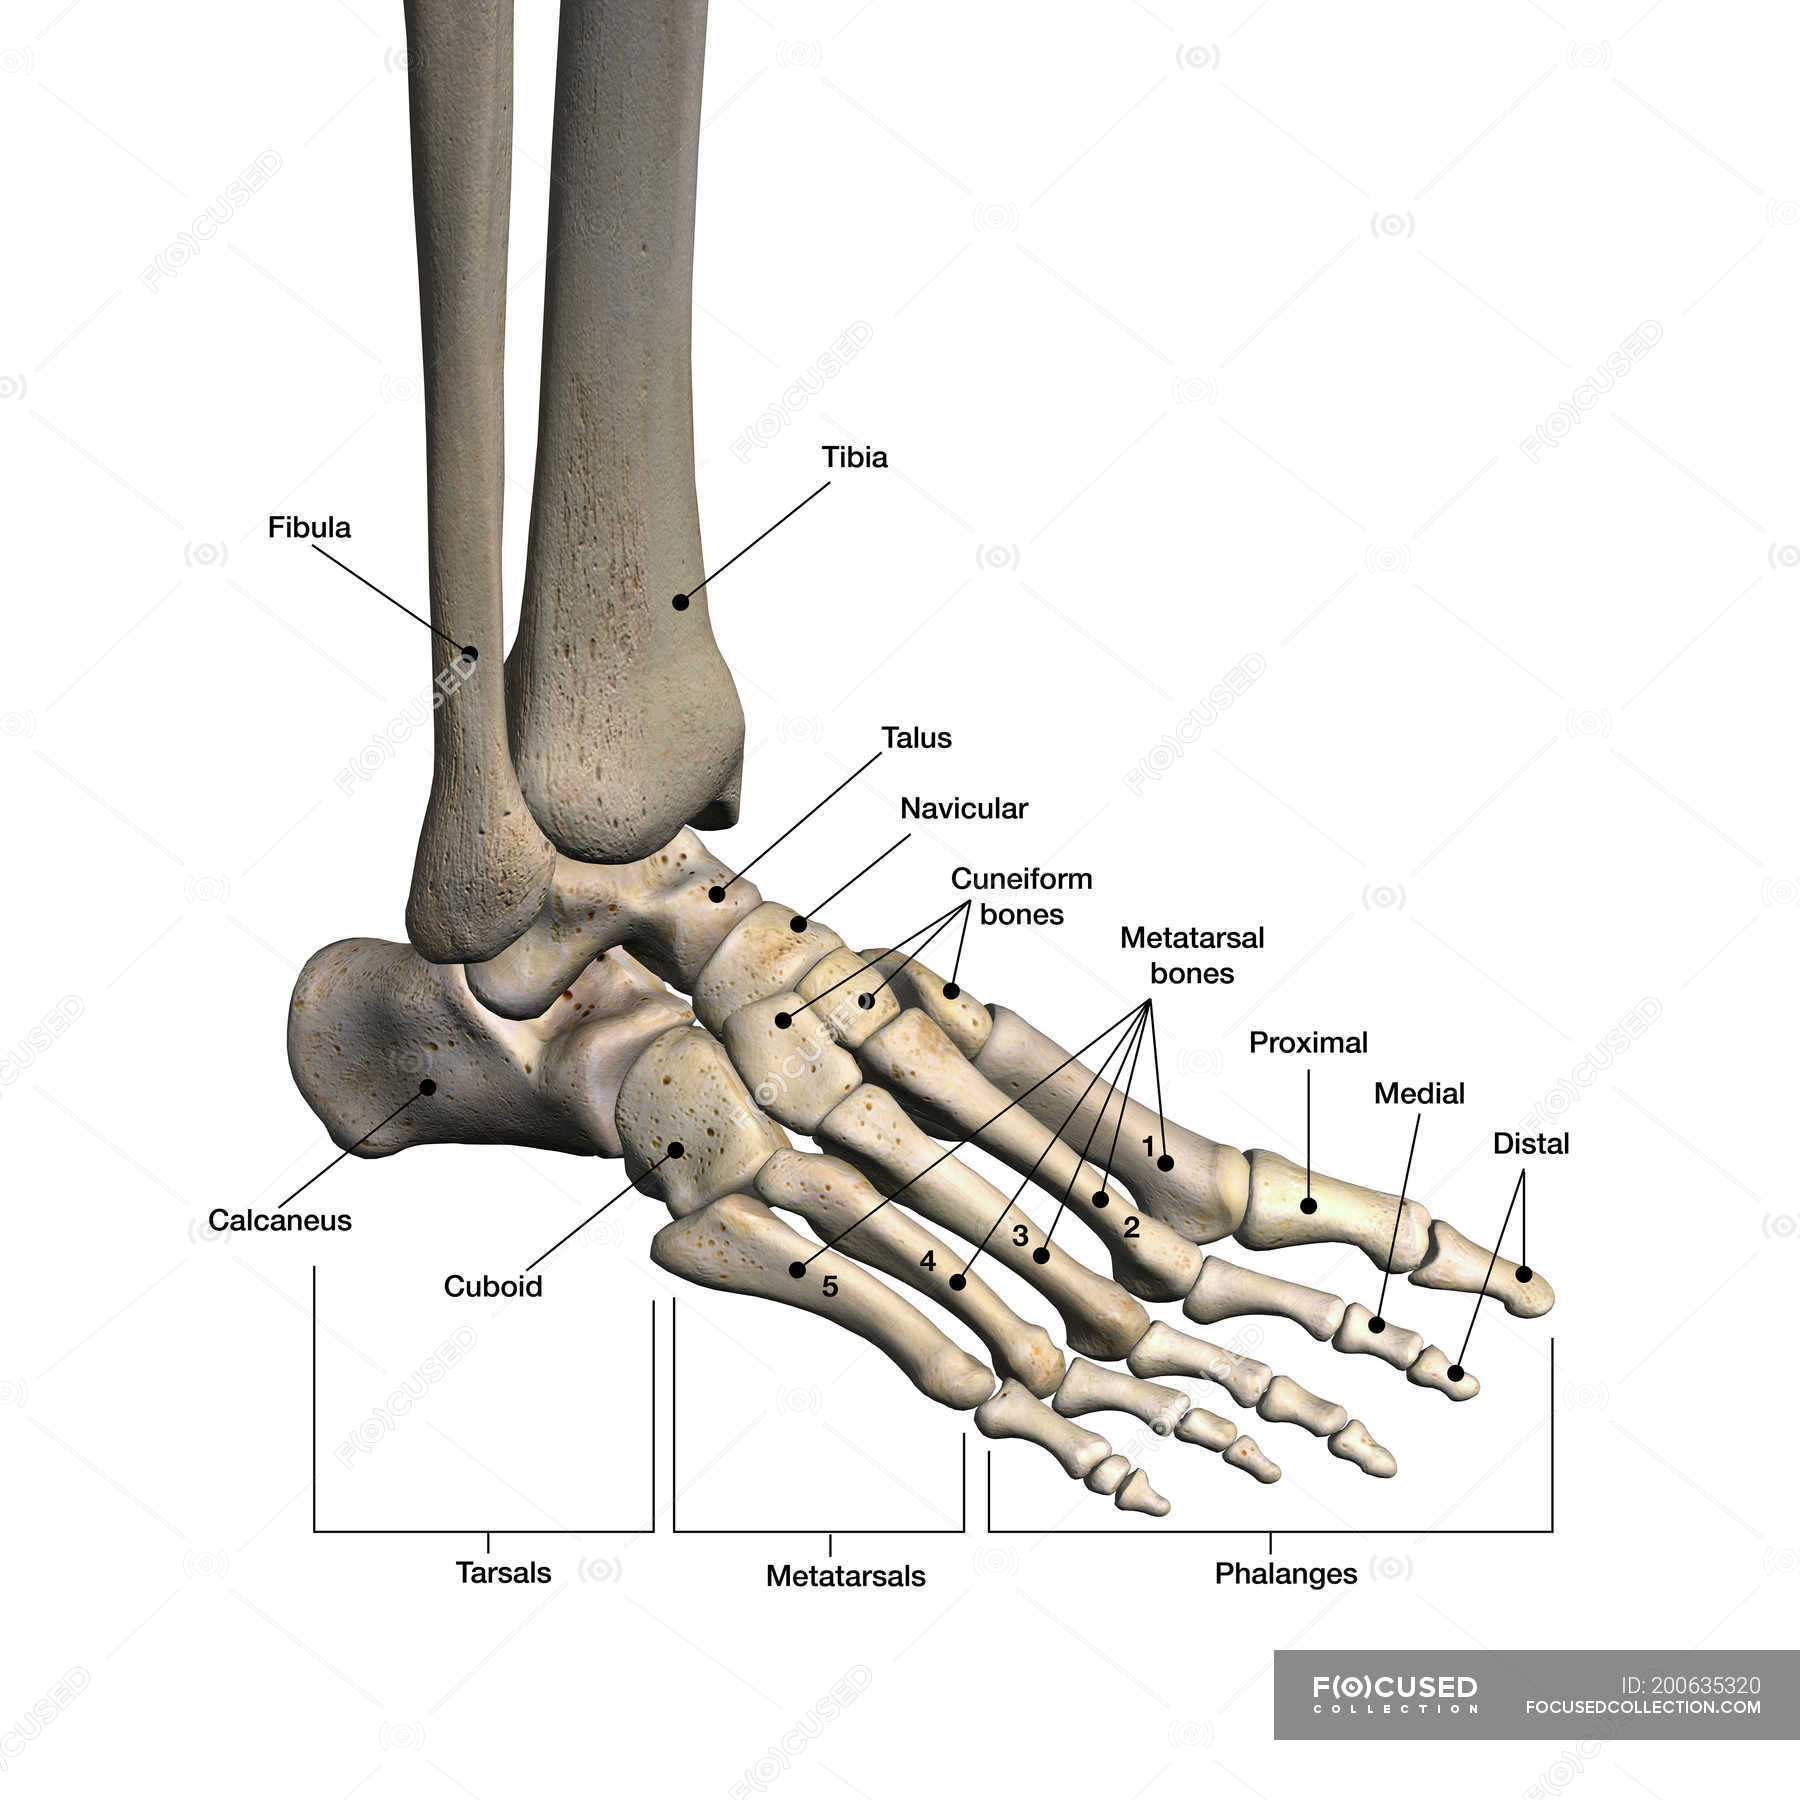

Foot Bones. Anatomy Of The Skeletal System Of The Human Legs And Feet

www.alamy.itBones Of Human Foot With Labels On White Background — Phalanx, Fibula

www.alamy.itBones Of Human Foot With Labels On White Background — Phalanx, Fibula

focusedcollection.comfoot bones human labels background fibula

focusedcollection.comfoot bones human labels background fibula